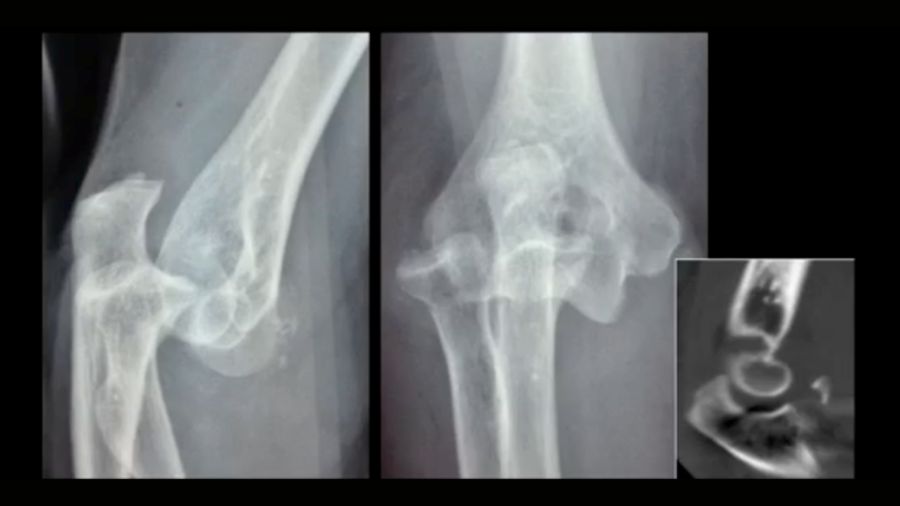

The coronoid fracture: classifying the damage

Shaun O’Driscoll’s coronoid classification system assesses the severity of coronoid fractures. The location and size of the fracture play a critical role in determining the treatment plan. For instance, a radial-sided tip fracture may not have as much impact on stability as a fracture involving the anteromedial facet.

The images demonstrate various coronoid fracture patterns, from minor tip fractures to complex fractures that involve multiple areas of the coronoid. Understanding the exact nature of these fractures—often via CT scans—is essential for effective treatment planning.

Case 3: 88-year-old woman

An 88-year-old patient with a terrible triad had an external fixator placed. A cemented prosthesis was chosen due to her age but encountered complications with cement leakage. Thankfully, no neurovascular damage occurred.